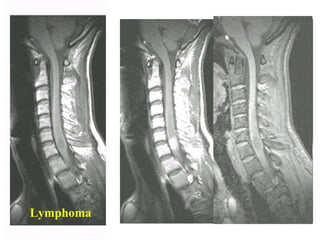

Di caên

Lymphoma